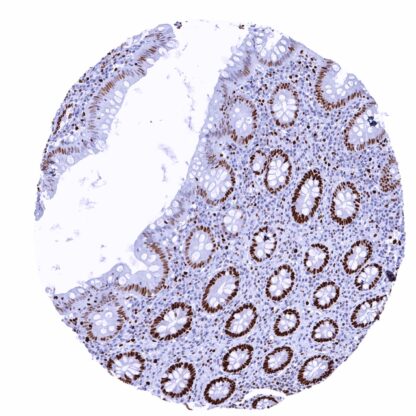

Recombinant Rabbit monoclonal / IgG 1:100 – 1:200 Research Use Only Nucleus Human MSVA-502R DNA replication licensing factor MCM2, Minichromosome maintenance protein 2 homolog, Nuclear protein BM28, BM28; CCNL1; CDC like 1; cdc19; CDCL1; Cell devision cycle like 1; Cyclin like 1; DNA replication licensing factor MCM2; KIAA0030; Minichromosome maintenance complex component 2; Minichromosome maintenance deficient 2 (mitotin); Minichromosome maintenance protein 2 homolog; Mitotin; Nuclear protein BM28 Colon: A strong nuclear MCM2 immunostaining should be seen in virtually all crypt base cells. Colon: MCM2 immunostaining should be less intense or absent in surface epithelial cells and absent in most stroma cells. MCM2 is a highly sensitive marker for proliferating cells. The MCM2 gene is located at 3q21.3 and codes for a nuclear protein which belongs to the highly conserved mini-chromosome maintenance proteins (MCM) 2-7 that play a key role in genome replication. They form a ring-shaped hexameric protein complex which unwinds double-stranded DNA, forms a replication fork during the initiation of DNA replication, and helps to recruit other DNA replication related proteins. The MCM2-7 limits DNA replication to a single occurrence per cell division and is critical for maintaining genome integrity. MCM2 is phosphorylated, and thus regulated by protein kinases such as CDC2 and CDC7. The MCM proteins are expressed in all cells in the G1, S, G2 and M-phase of the cell cycle but in contrast to the better established proliferation marker Ki-67, MCMs are already expressed in early G1 phase. This results in the detection of more proliferating cells as compared to Ki67 immunohistochemistry which might be advantageous in tumor types with low proliferative activity. Images describing the MCM2 staining pattern in normal tissues obtained by the antibody MSVA-502R are shown in our “ Normal Tissue Gallery ”. Brain Cerebrum Negative. Cerebellum Negative. Endocrine Tissues Thyroid Weak to moderate MCM2 staining of a small fraction of follicular cells. Parathyroid MCM2 staining in a small fraction of epithelial cells. Adrenal gland A variable MCM2 staining occurs in a small fraction of adrenocortical cells. Pituitary gland Weak MCM2 staining in a small fraction of cells (neuro- and adenohypophysis). Respiratory system Respiratory epithelium Significant MCM2 staining in a fraction of (mostly basal/suprabasal) respiratory epithelial cells. Lung Strong MCM2 staining of a large subset of pneumocytes. Gastrointestinal Tract Salivary glands Weak MCM2 staining in a fraction of epithelial cells. Esophagus Moderate to strong MCM2 staining of suprabasal and basal cells of the squamous epithelium. Stomach Strong MCM2 immunostaining of many mucous neck cells. Duoden... A nuclear MCM2 immunostaining in a fraction of tumor cells is always seen in cancerous tissues. The TCGA findings on MCM2 RNA expression in different tumor categories have been summarized in the Human Protein Atlas. Adenocarcinoma (Gleason 3+3=6) with weak to moderate MCM2 positivity of fewtumor cells Squamous cell carcinoma with strong MCM2 staining of almost all tumor cells Follicular adenoma with variable MCM2 staining of a fraction of tumor cells Cancer tissue gallery No data available at the moment IHC users have different preferences on how the stains should look like. Some prefer high staining intensity of the target stain and even accept some background. Others favor absolute specificity and lighter target stains. Factors that invariably lead to more intense staining include higher concentration of the antibody and visualization tools, longer incubation time, higher temperature during incubation, higher temperature and longer duration of the heat induced epitope retrieval (slide pretreatment). The impact of the pH during slide pretreatment has variable effects and depends on the antibody and the target protein. All images and data shown here and in our image galleries are obtained by the manual protocol described below. Other protocols resulting in equivalent staining are described as well. Manual protocol Freshly cut sections should be used (less than 10 days between cutting and staining). Heat-induced antigen retrieval for 5 minutes in an autoclave at 121°C in pH 7,8 Target ... The prognostic role of the percentage of MCM2 positive cells is yet unknown. It is unclear whether MCM2 quantification is equally or better suited than the established Ki67-Li for prognosis assessment in tumors with rather low proliferation rate. In principle, there are two ways how the specificity of antibodies can be documented for immunohistochemistry on formalin fixed tissues. These are: 1. Comparison with a second independent method for target expression measurement across a large number of different tissue types (orthogonal strategy), and 2. Comparison with one or several independent antibodies for the same target and showing that all positive staining results are also seen with other antibodies for the same target (independent antibody strategy). For proteins such as MCM2 which are expressed in virtually all tissues but restricted to specific cell types and cell compartments, orthogonal validation is not well suited. However, the comparison of MSVA-502R immunostaining data with data from three independent RNA screening studies, including the Human Protein Atlas (HPA) RNA-seq tissue dataset, the FANTOM5 project, and the Genotype-Tissue Expression (GTEx) project, which are all summarized in the Human Protein Atlas (Tissue ...